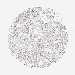

BRCA TCGA BRCA VALIDATION PROTEIN EXPRESSION

ANTIBODIES

AND

VALIDATION